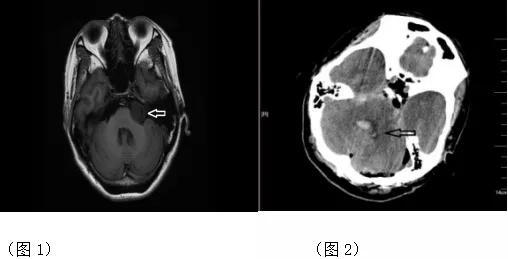

患者,女,因左耳听力下降20年余,头痛20天,加重1天,以听神经瘤(图1)于2019.08.05 09:16收入院,既往“高血压”病史20年,血压高时达170/100mmHg,平素服用“硝苯地平缓释片,10mg,bid”治疗,血压控制尚可。2019.08.07 07:50去手术室在全麻下行左侧桥小脑角占位性病变开颅切除术,于17:10患者返回病房,术后患者全麻未醒,双瞳孔直径4mm,对光反应迟钝,肢体松弛,给予心电监护监测生命体征,17:25患者血压177/110mmHg, 患者呼之不应,刺痛屈伸,肌张力高,发出*吟呻**,通知医师,17:30遵医嘱给予降压药物NS 50ml+乌拉地尔100mg泵入,设置泵速5ml/h,17:45再次巡视患者,发现患者鼾式呼吸,患者双瞳孔直径5mm,对光反应迟钝,刺痛无*吟呻**,测血压181/105mmHg,通知医师,遵医嘱给予急查颅脑CT,CT示脑出血破入脑室(图2),于18:30去手术室在局麻下行侧脑室穿刺引流术,19:10患者安返病房,嗜睡状态,双瞳孔直径4mm,对光反应灵敏,呼之睁眼,回答问题正确,四肢肌力、肌张力均正常。

1. 患者全麻术后,呼之不应,误以为全麻未醒状态,血压177/110mmHg,仍认为术后搬运病人导致,测量血压偏高,告知医师,遵医嘱给予降压药物乌拉地尔泵入,但血压仍持续升高,意识较之前更差,故急查颅脑CT,CT示脑出血破入脑室。